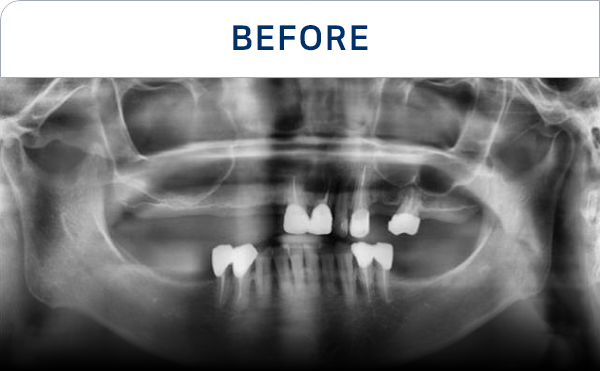

准确掌握口腔状况

了解所需的治疗方向

通过CT, 扫描等数字设

备拍摄后,

进行精密分析

种植牙是一项高难度治疗,

需依赖精密检查与充分的术前计划

因此, 选择具备丰富经验与专业技术的

医疗团队尤为重要